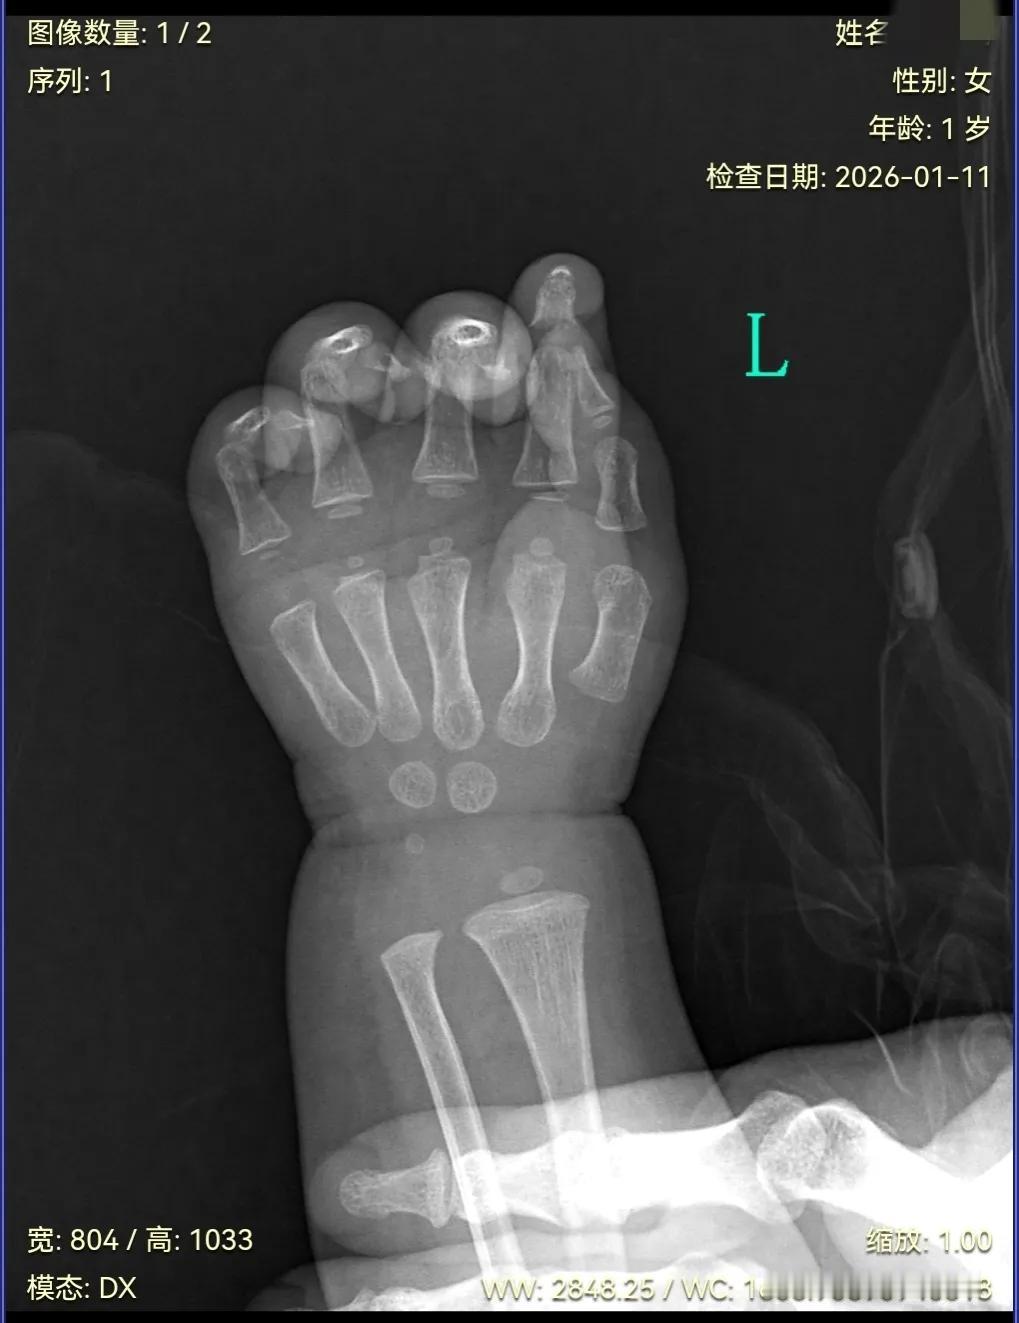

难以释怀,当奶奶的人,看小孩几分钟时间,就认为小孩手是摔肿的,我也在旁边, 根本没有摔,一直跟医生解释是摔了,非要照这个。 当时小孩都发烧了,我都是认为不舒服才造成的。 一直耽误时间,检查这个对身体又不好,我不让检查这个,还不行,因为医生听小孩奶奶的话。 检查出来,一点事都没有。 孩子一直都是我自己带着,她什么样的我难道不知道吗。 我也不太清楚照了这个,到底对身体有没有害处。 求懂得人分析一下。